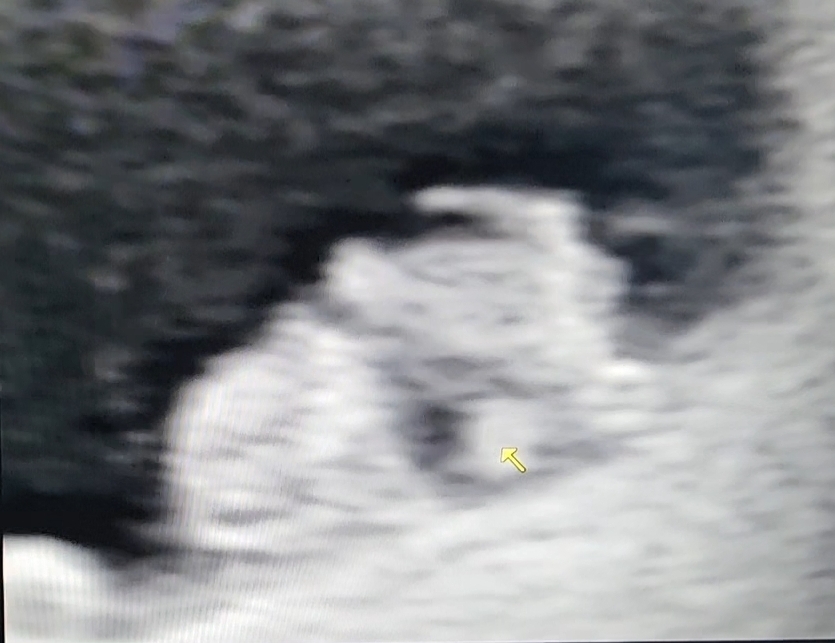

8주 0일이라 기대 안하고 있었는데 나올랑말랑한 팔다리라며 보여주셨어요 ㅋㅋㅋㅋ 짧뚱한게 넘 웃겨요🤣